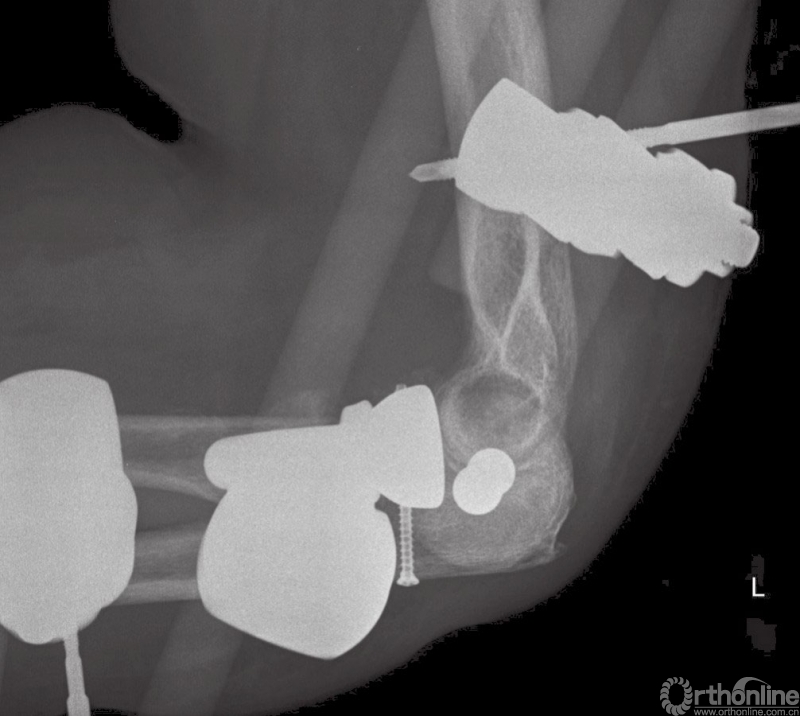

初始治疗措施包括局麻下闭合复位并用夹板固定。手术治疗依据复位后拍摄的肘关节前后位及侧位X线片,常规进行CT检查,通过CT扫描可以直观地了解冠状突及桡骨头的骨折大小及范围。同时行三维CT检查对评估损伤也十分有帮助(图2)。

图2 侧位片提示肘关节脱位,桡骨头骨折,冠状突Ⅲ型骨折